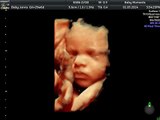

3d 4d baby scans www.scan4d.co.uk